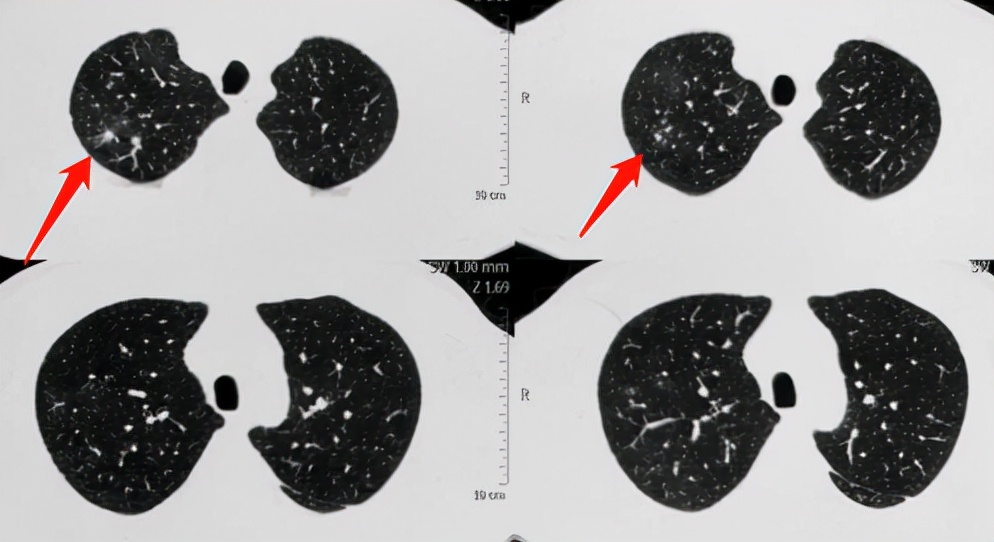

结果4个月后,出现咳嗽、痰中带血,回医院复查CT,发现病灶明显增大、增多了:

上肺有几个白色小结节,周围有一圈模糊的磨玻璃影,就像光晕一样(晕征)。

1.结节肿块型,表现为单发或多发的结节或肿块(肉芽肿性炎),边界清晰或者伴有晕征,当伴有晕征时提示意义较大。需要留意:这种类型常常被误诊为肺癌或者肺结核,因为它也常出现毛刺、空洞、支气管截断征等等,我们后面会讲鉴别诊断。